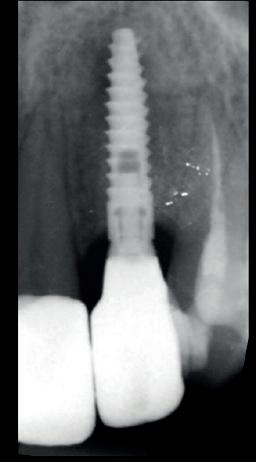

In deze casus is extractie van de 37 geïndiceerd in verband met een fistel en restpockets, zoals zichtbaar op de röntgenfoto’s (afbeelding 1). Duidelijk te zien is de forse peri-apicale ontsteking en het botverlies bij de 37, dat zowel richting buccaal als linguaal doorloopt. De 37 wordt atraumatisch verwijderd. Er is aan de linguale zijde veel bot verloren en er is sprake van een perforatie aan de buccale zijde.

Er wordt besloten om botmateriaal te plaatsen in de extractie-alveole. Vervolgens wordt het afgesloten met een titanium versterkt d-PTFE membraan (afbeelding 2). Na vier weken wordt het membraan verwijderd.

Zes maanden na extractie wordt het implantaat 37 geplaatst. Er is sprake van een goede genezing en de processushoogte en -breedte zijn behouden en opgebouwd. Ook is er zichtbaar gekeratiniseerd weefsel

gewonnen. De wond kan na het plaatsen van een healing abutment primair gesloten worden (Afbeelding 3a-3d).

In afbeeldingen 4a-c is het resultaat drie maanden na het plaatsen van het implantaat te zien. De genezing is volledig en de verwijzer kan de suprastructuur vervaardigen (afbeelding 4a-4c).

In afbeeldingen 5a-d is de implantaatkroon 37 te zien, twee jaar na plaatsing. Op de röntgenfoto is herstel van zowel corticaal als spongieus bot te zien. (De CB-CT was vervaardigd in verband met implantologische indicatie in het naastliggende gebied).